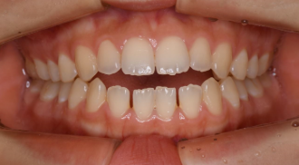

マウスピース型矯正装置(インビザライン)の症例

マウスピース型矯正装置(インビザライン)を使用した歯列矯正

ガタガタ(叢生)